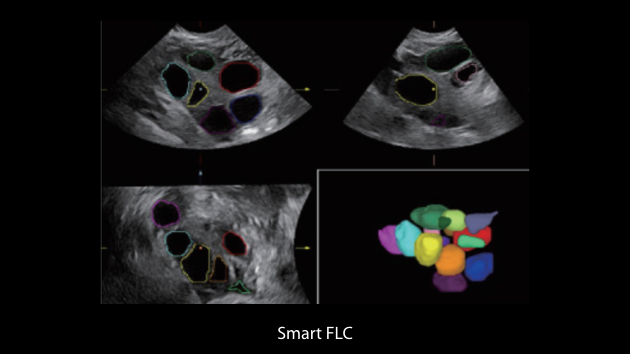

The Nuewa I9, dedicatedly designed for women and neonatal healthcare, providing an innovative experience from inside out.?These innovations are developed based on in-depth insights into complex clinical scenarios, providing accurate and timely answers as well as outstanding efficiency and remarkable user experience.

Clinical Images